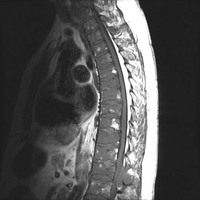

MRI: Sag T1 and STIR of T-spine

Sagittal T1 and STIR images of the thoracic spine demonstrate diffusely abnormal T1 hypointense signal throughout the visualized marrow and areas of patchy STIR hyperintensity relating to marrow edema due to myelomatous involvement, most conspicuous at the T12 level, along with T6 vertebral body and T2 spinous process involvement.  Moderate compression deformity of T6.